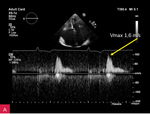

W badaniu przedmiotowym stwierdzono szmer skurczowy nad koniuszkiem, trzeszczenia nad polami płucnymi oraz obrzęki podudzi. W zapisie elektrokardiograficznym zarejestrowano migotanie przedsionków ze średnią częstością rytmu komór 40/min. W badaniach laboratoryjnych poza podwyższonym stężeniem N-końcowego fragmentu propeptydu natriuretycznego typu B (NT-proBNP – N-terminal pro-B-type natriuretic peptide – 1437,0 pg/ml) nie stwierdzono istotnych nieprawidłowości. W badaniu rentgenowskim klatki piersiowej uwidoczniono znaczne poszerzenie sylwetki serca (CTR – cardiothoracic ratio – 0,69) oraz dobrze wysycone zacienienie o wielkości przekraczającej 20 × 40 mm widoczne w rzucie serca.